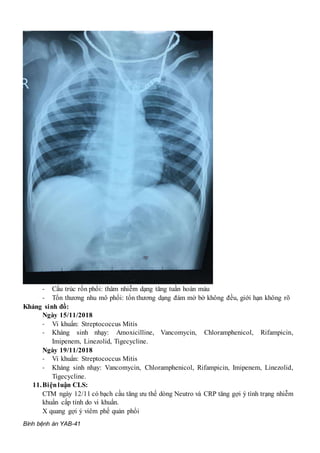

X-quang ngực thẳng: ngày 12/11/2018

- Cấu trúc rốn phổi: thâm nhiễm dạng tăng tuần hoàn máu

- Tổn thương nhu mô phổi: tổn thương dạng đám mờ bờ không đều, giới hạn không rõ

X quang gợi ý viêm phế quản phổi